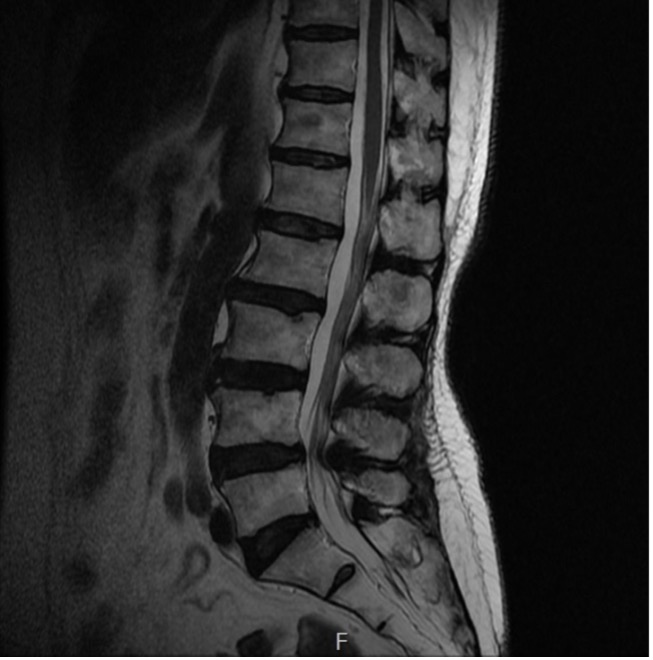

수술 전

수술 후